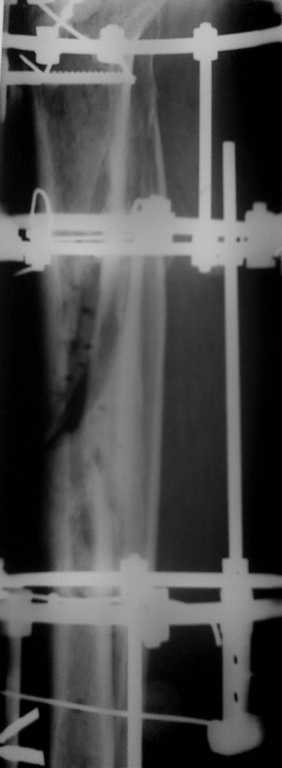

Больной получил травму около 1 года назад 24.09.07.

Обратился вовремя, но началась Белая горячка и больной на скелетном

вытяжении, в общем за неделю (в свинячем поведении)повредилась

клетчатка, травма кожи. Прооперировали через 14 дней после улучшения

состояния, смещение устранено, стояние отломков хорошее, но появилось

осложнение некроз кожи до 15см! В течение года проводилось дважды

пластика кожи по Тиршу, свободным лоскутом, Тунелизация по БЕКУ.

Нагружает конечность в пределах 50%, больше не хочет! На данный

момент отмечается мозоль там где есть кожа. А по передней поверхности

в области язвы нет. В динамики почти за год кожный дефект нарос. Что

предпринять? Посоветуйте. Один хочет оперировать! Удалять дефект, но

ведь нет кожного лоскута, чем укрыть?